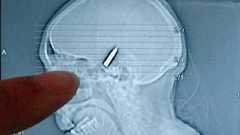

中国の江蘇省で、頭痛に悩まされて病院に来た77歳の女性の頭をX線で撮影してみたところ、なんと頭の中に銃弾があることが発覚しました。しかもその銃弾は64年前に銃撃を受けたときに頭の中に残ったものとのこと。 手術してさび付いた銃弾を取りのぞいた外科医は、銃弾が頭に大した問題を引き起こさないで残っていたことに驚いたそうです。当たり前ですねそりゃ…。 詳細は以下から。 Woman had bullet in head for 64 years | Weird Asia News この記事によると、今回頭に銃弾が残っていたJin Guangyingという77歳の中国人女性は、第二次世界大戦中の1943年に、ゲリラをしていた父親に物資を届けに行ったところを日本軍の銃撃に巻き込まれたそうです。当時彼女は13歳だったとのこと。 彼女は頭に銃弾を受けた際に意識を失いましたが、母親が生薬を傷口に塗ったところ、